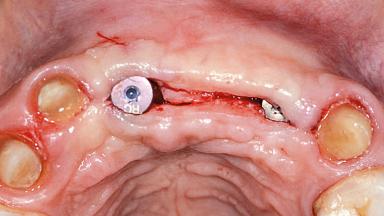

A 38-year-old woman presented with an esthetically unacceptable fixed partial denture replacing teeth 11, 21, 22. She had lost these teeth due to trauma when she was a child. The patient was not in pain but very concerned based on her previous experience that dental treatments had never satisfied her esthetic expectations. She was in good general health and reported no regular medications. No periodontal disease was noted despite the fact that the buccal flange of the prosthesis impeded cleaning of the tooth abutments. The patient did not smoke and complied with home maintenance requirements, as evidenced by her good oral hygiene status.